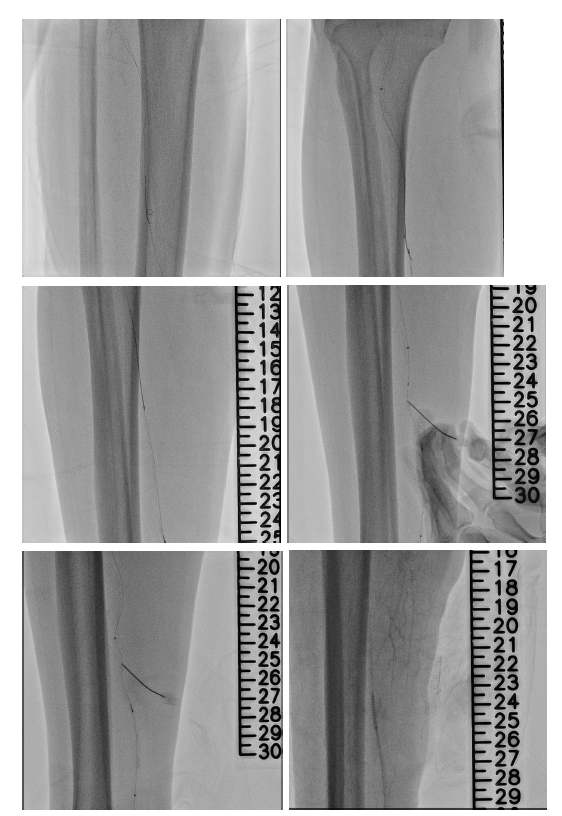

From a right femoral approach to RCFA, we used 0.014" GLADIUS GW with Oscar¢ç multifunctional peripheral catheter initially and changed wire to ASTATO XS40 GW to wiring the infrapopliteal CTO targeting the posterior tibial artery. However, even under strong support of Oscar¢ç multifunctional peripheral catheter, we still could not antegrade wiring through. Therefore, we performed a retrograde puncture to distal posterior tibial artery. We used 0.014" GLADIUS GW with CXI microcatheter and Knuckle technique to retrograde approach proximal posterior tibial artery. Successful rendezvous was achieved, confirming passage through the CTO segment. Balloon passage through the distal PTA lesion was difficult due to tight stenosis. So, several attempts with needle cracking technique on the distal PTA lesion was done, following serial balloon dilatation to PTA. Distal PTA perforation occurred secondary to excessive needle cracking. Several attempted hemostasis were performed following distal PTA perforation but in vain. A covered stent was deployed to seal the distal PTA perforation. Final angiography showed successful revascularization to PTA CTO.